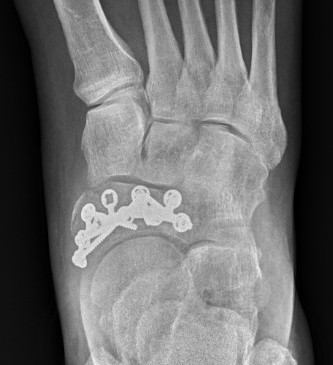

Locking plate

Paragon navicular plate Synthes navicular plate

AO foundation navicular locking plate technique

Paragon Baby Gorilla navicular plates PDF

Displaced stress fracture treated with dorsal plate